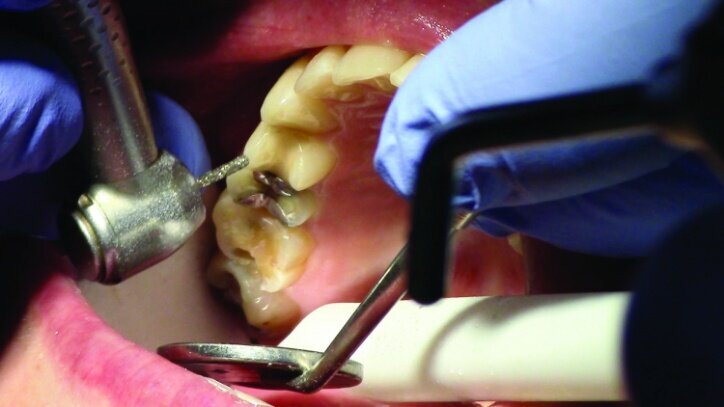

Depth guide cuts were made using a 330 bur, which has a 2 mm cutting surface (Figs. 2a–3b). This ensures 2 mm of occlusal reduction to accommodate 2 mm of material thickness on the occlusal surface of the restoration.

Gross occlusal reduction was completed using a KS7 bur to the depth cuts (Figs. 4–8b, 9c). Adequate clearance was verified with a 2 mm prep check from Common Sense Dental Products.

The remainder of the existing composite resin in #3 and the amalgam in #4 were removed. The occlusal surfaces of the preparations were blended into the interproximal areas using a KS2 bur to create smooth preparations (Figs. 10–15c). There was no retention or resistance form prepared to retain the restorations.